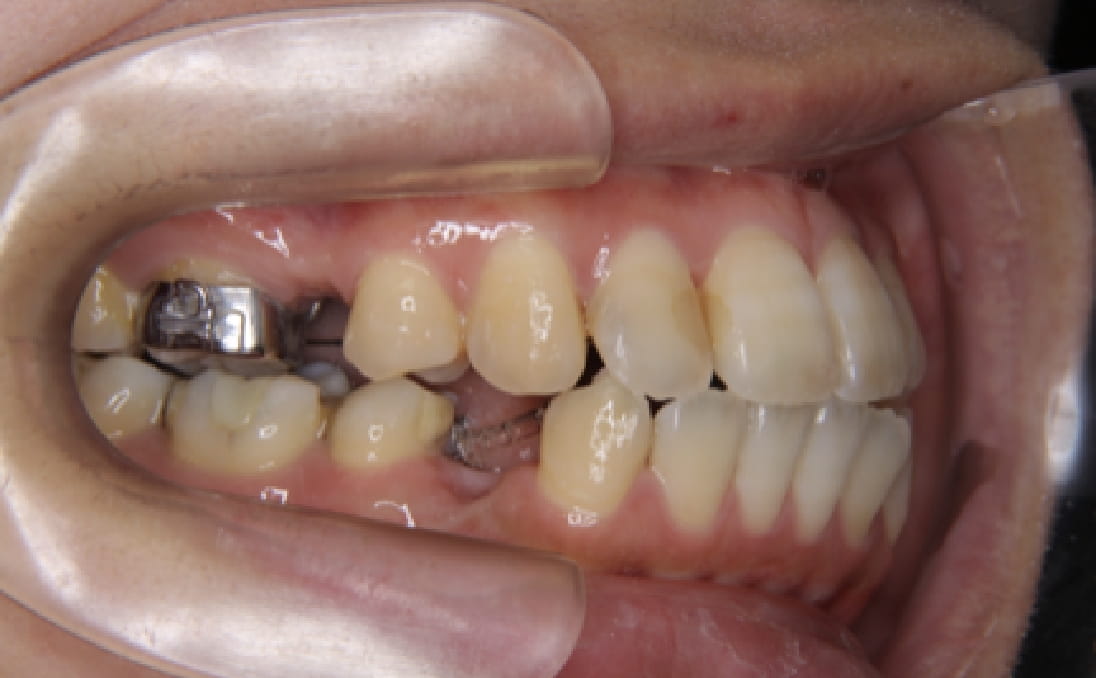

《歯槽性上下顎前突を伴う叢生》

症例42

性別:女性 年齢:13歳 お住まいの地域:奈良市

主訴 上の2本が出てるのが気になる

治療装置 上裏側、下表側からのハーフリンガル矯正装置

抜歯 上下4本

治療期間 2年8ヶ月

診断名 歯槽性上下顎前突を伴う叢生

副作用 歯肉退縮・歯根吸収・歯髄壊死・癒着による予期せぬ歯の動き

より綺麗にする希望を達成するために上下4本を抜歯。前歯のリトラクション(後方移動)を行うためにインプラントを使用。若年層ではあるが、インプラントの安定がよく、ヘッドギアに切り替えることなく、順調に進められた。

治療中(23ヶ月後)